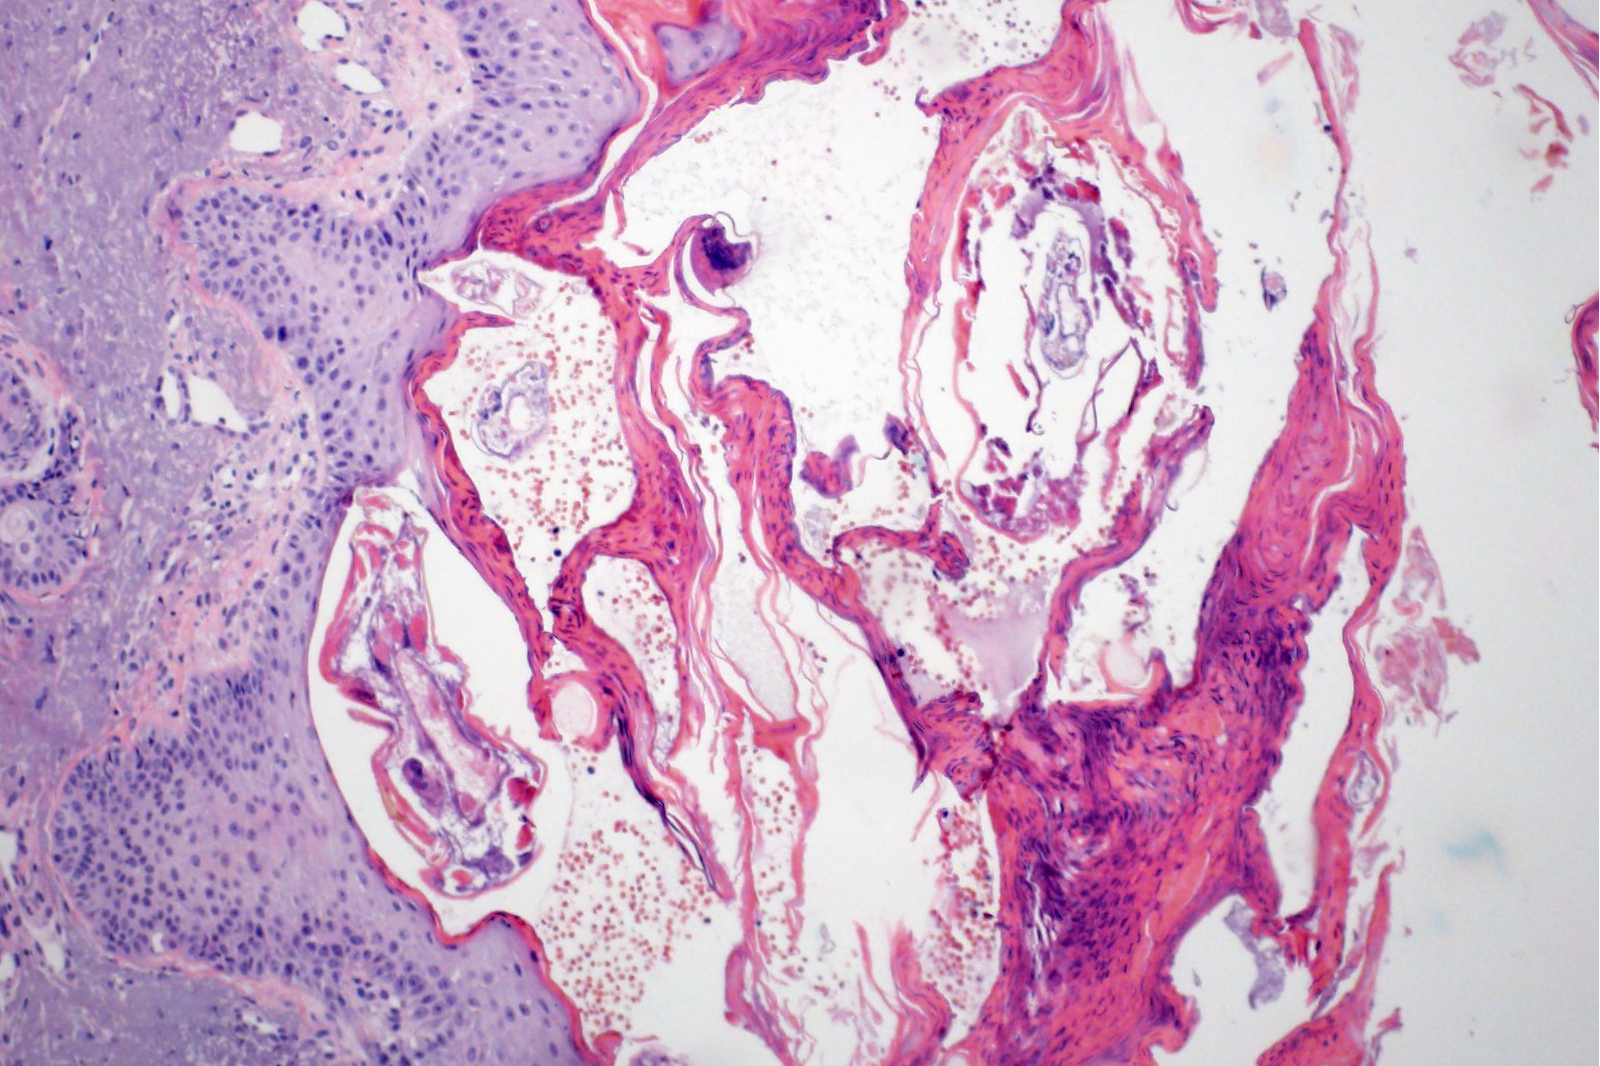

Laboratório Santa Clara é referência em Patologia, Citologia e Biologia Molecular. Aqui você encontra qualidade certificada, tecnologia e respeito por nossos parceiros e pacientes.

BIOLOGIA MOLECULAR

Diagnósticos avançados através da análise de DNA para detecção precoce de infecções, HPV, ISTs e alterações genéticas. Aqui tem!